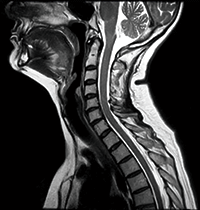

The vital pulse sequences, acquisition features and post processing tools for high-quality imaging of head/neck and spinal structures are standard on Oasis. ADAGE (combined gradient echo) and isoFSE deliver high contrast, high SNR acquisitions providing detailed visualization of spinal abnormalities. Advanced neurological imaging includes susceptibility imaging, perfusion, spectroscopy and more.

RADAR T2 FSE

3D primeFSE acquisition with volume rendered reformat